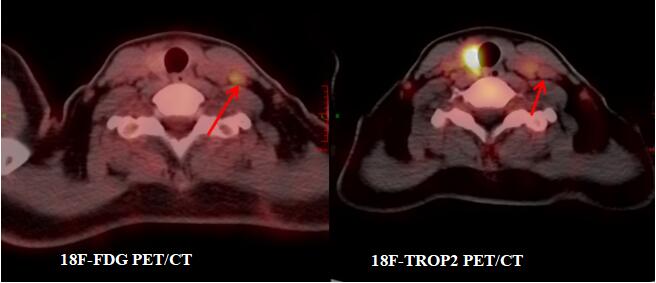

(江叶青报道)近日,江西省肿瘤医院核医学科收治一名甲状腺癌二次手术患者宋某。2022年,宋某因颈部包块在当地医院行左侧甲状腺癌根治术,术后病理确诊为甲状腺微小乳头状癌。出院后定期随访复查,但今年9月复查显示颈部淋巴结转移可能,10月,患者转入江西省肿瘤医院头颈肿瘤外科二病区接受右侧甲状腺手术及颈部淋巴结清扫,术后病理提示右侧甲状腺亦为微小乳头状癌,且颈部淋巴结存在转移性病变。为评估病情并指导后续碘-131治疗,同期为患者行18F-FDG与18F-TROP2 PET/CT显像,结果呈现鲜明对比:

左侧锁骨上窝淋巴结:FDG代谢增高,但TROP2代谢未见增高,穿刺洗脱液Tg检测为阴性(0.124 ng/ml)。提示该FDG高代谢灶可能为非肿瘤性(如炎症)。

左侧颈部III区淋巴结:FDG代谢未见增高,但TROP2代谢明显增高,穿刺洗脱液Tg检测强阳性(7658 ng/ml)。明确为隐匿的甲状腺癌转移灶。